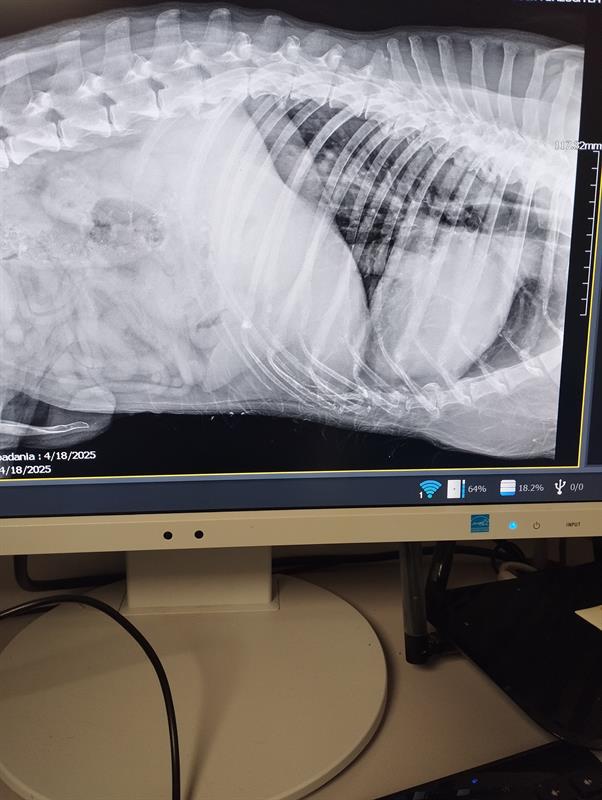

Pies leżał tuż przy drzwiach. Na podłodze. Miski z wodą i jedzeniem stały opodal. Ale on nie był w stanie się podnieść. Nie miał dość siły, żeby stać. Fot. Towarzystwo Opieki nad Zwierzętami

Leżał na podłodze. Przy pełnych miskach. I nie był w stanie się podnieść z własnych odchodów. Odór gnijącego mięsa - jego nabrzmiałego i ropiejącego guza przy zadzie - czuć było już na półpiętrze, tuż przed mieszkaniem, w którym… w potwornym bólu otwartych ran, odparzeń i odleżyn dogorywał, bez pomocy, miesiącami. Pies Junior.